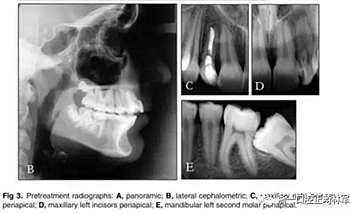

全景X線(圖3)顯示所有牙齒均存在,包括第三磨牙的牙胚。左下頜第二磨牙近中阻生。X線片顯示以前根管治療的上頜右側(cè)切牙(據(jù)報道有窩溝內(nèi)陷),對側(cè)切牙有根尖周圍病變以及窩溝內(nèi)陷的典型影像學(xué)表現(xiàn)。上頜中切牙的根部顯示先前存在的吸收。頭影測量分析顯示上頜骨和下頜骨矢狀和垂直關(guān)系正常。上頜和下頜門牙過度唇側(cè)傾斜。